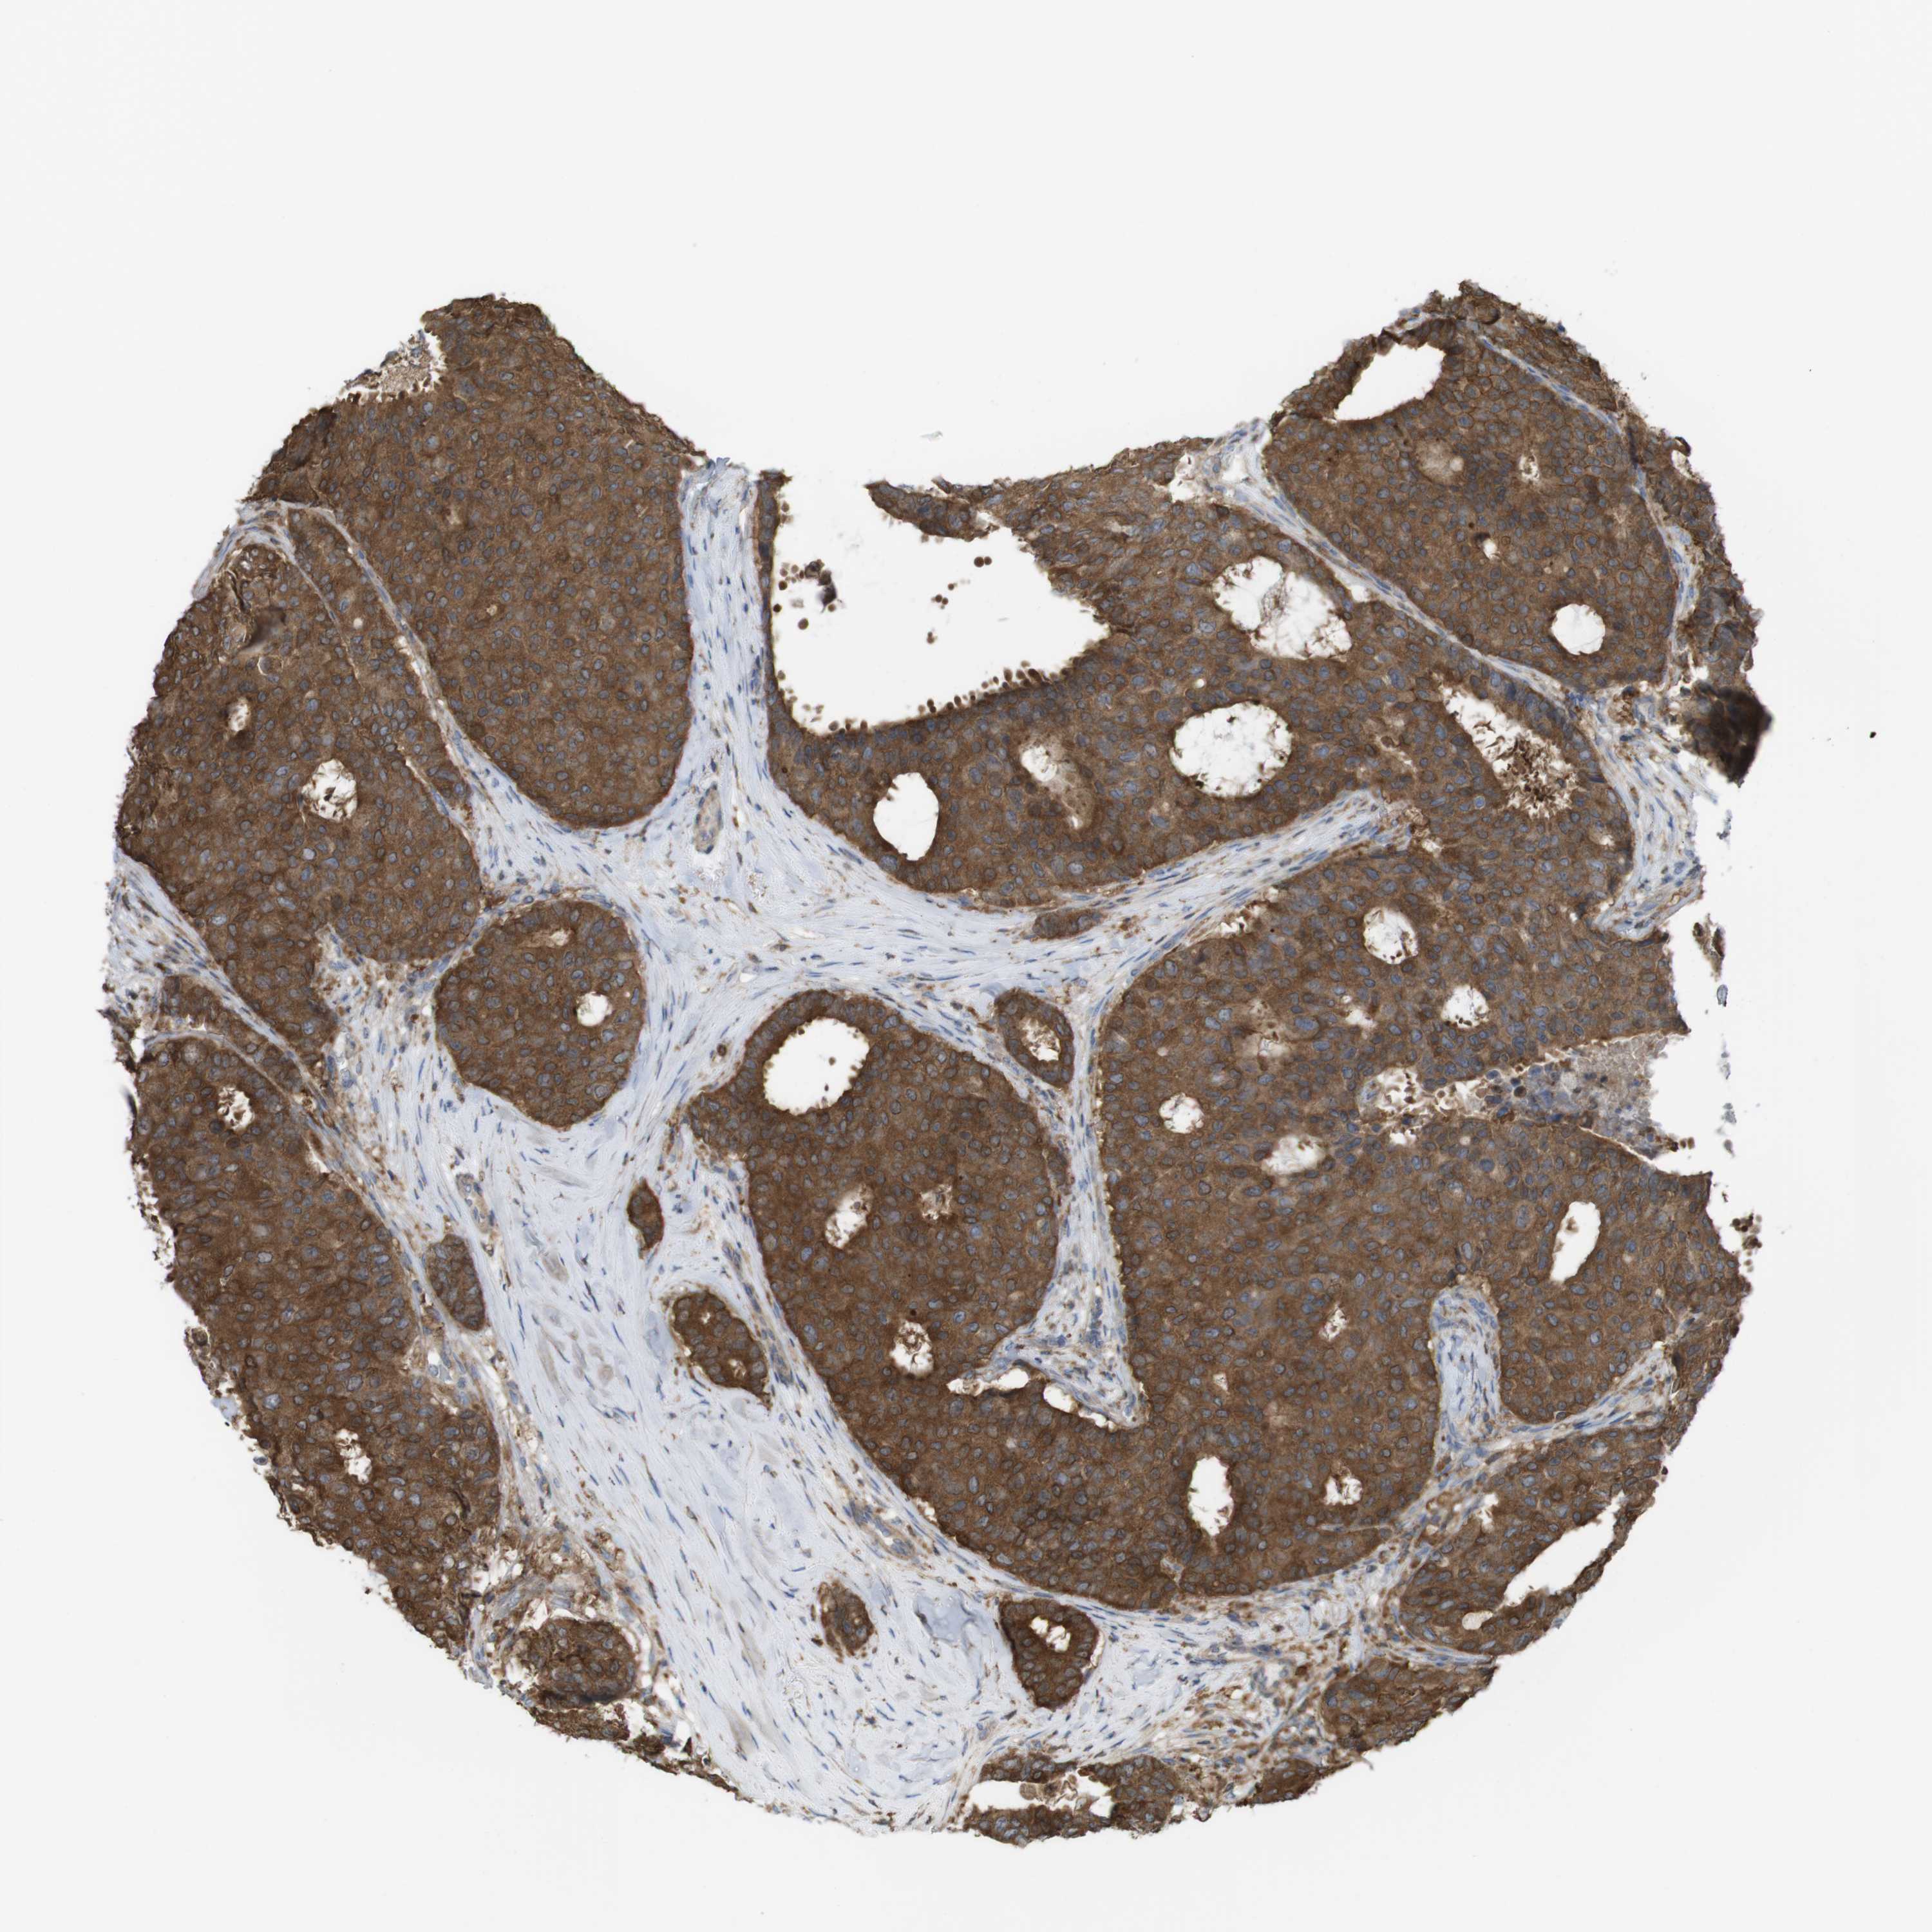

BRCA TCGA BRCA VALIDATION PROTEIN EXPRESSION